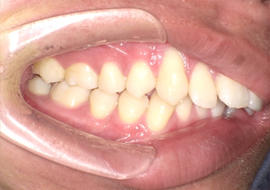

症例4

Before

After

| 主訴 | 上下前歯のがたつき |

|---|---|

| 年齢 | --- |

| 治療 期間 |

約9ヶ月 |

| 治療 内容 |

インビザラインiGoで上下顎の治療。 |

| 治療費 | ¥550,000(税込)/調整料含む |

| 治療のリスク | 矯正終了後は、リテーナーを指示通りに使用し、歯の後戻りを防ぐ必要があります。 |